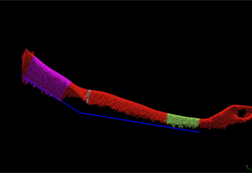

ハンディ3Dスキャナーは静止した物だけでなく、動く(移動する)対象物も撮影して、画面ごとにサーフェースモデルを作成します。変化する体(腕や背中など)を撮影し、リハビリでの改善状況の把握に役立てます。また、部品の変位移動量(振動するケーブルや部品の挙動など)を3D解析することで、これまで実行できなかった製品のシミュレーションが可能となります。

特集 ハンディ3Dスキャナーをリハビリで利用する

1. 従来のマニュアル測定方法に代え、非接触ハンディ3Dスキャナーで関節の曲がり状態を調べる。